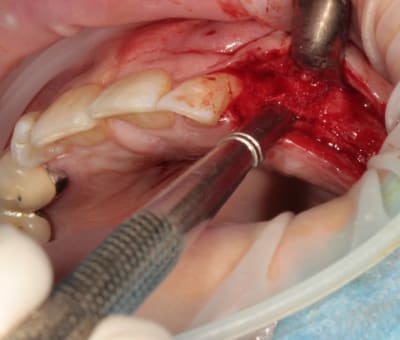

2:

Ostéotome "lame" angulé

lame 15 (fréquent dans ce cas )

Ostéotome droit

tous sont manipulés avec douceur, mais aussi impactés avec le maillet chirurgical